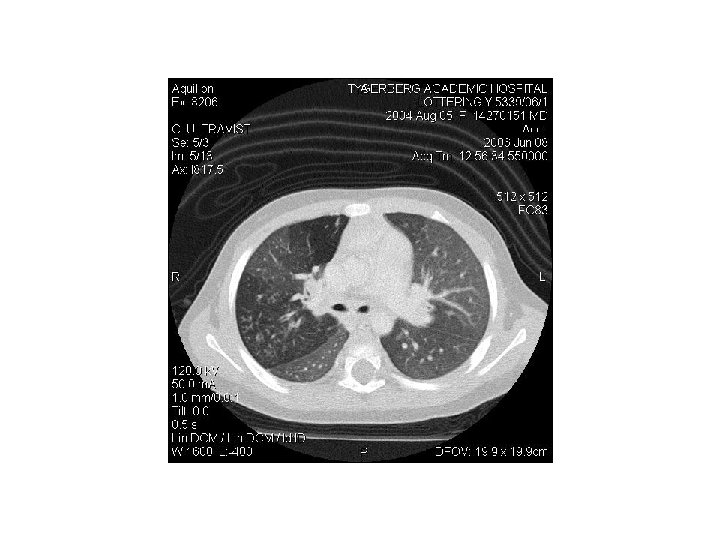

Chest X-ray in severe asthma • Relevant in search for underlining complications – Pneumonia – Air leakages – Collapse • Ventilated patients

Asthma complications • • • • Pneumothorax Pneumomediastinum Pneumopericardium Pulmonary interstitial emphysema Pneumoretroperitoneum Cardiac arrhythmias Myocardial ischaemia or infarction Mucus plugging Atelectasis Pneumonia Electrolyte disturbances – Hypokalaemia – Hypomagnesaemia – hypophosphataemia) Lactic acidosis Hyperglycaemia Theophylline toxicity